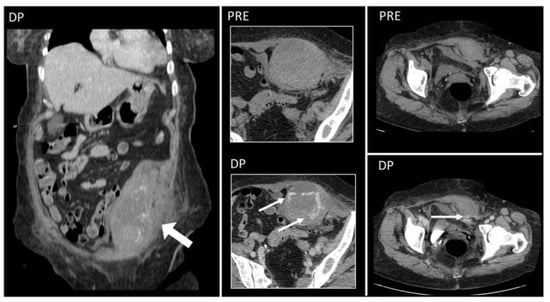

Figure 13. Non-enhanced sagittal and axial CT scan demonstrates free silicon material scattered with an infiltrative appearance, expanding all along the subcutaneous fat of the posterior abdominal wall (arrows). Strand-like lesions coexist with nodular and plaque-like areas, making the differential diagnosis with neoplastic conditions difficult.

Free silicone and paraffin are seen as irregularly scattered collections extended along fascial planes, mimicking sarcomatous or metastatic processes [38,39].

On US, they are heterogeneously echoic, with marked posterior acoustic shadowing [39]. On CT, their diffuse infiltrating appearance is well seen, with solid density but a lack of contrast uptake, accompanied by fat stranding [37,38] (Figure 13).